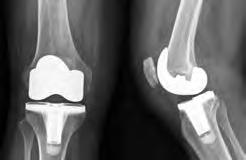

El reemplazo total de rodilla también se denomina artroplastia total de rodilla. Se trata de una operación que se realiza para quitar y reemplazar (o recubrir) las partes desgastadas de la articulación de la rodilla. La rodilla está formada por el extremo inferior del fémur, el extremo superior de la tibia, y la rótula (patela), la cual se desliza en una ranura en el extremo del fémur. Los ligamentos grandes están adheridos al fémur y a la tibia para brindar estabilidad. Los grandes músculos del muslo le dan fortaleza a la rodilla. Las superficies de la articulación donde entran en contacto estos tres huesos están cubiertas con cartílago articular, el cual amortigua los huesos y permite su movimiento sin dificultades. Una membrana delgada libera un líquido especial que lubrica la rodilla, lo cual reduce la fricción durante el movimiento. Normalmente, todos estos componentes funcionan en armonía. No obstante, las enfermedades y las lesiones generan dolor, debilidad muscular y un funcionamiento reducido. Si tiene estos problemas, es posible que necesite un reemplazo total de rodilla.

Durante el reemplazo total de rodilla, se eliminan las superficies dañadas de la articulación de la rodilla y se las sustituye con un implante. Dicho implante puede estar hecho de metal o de plástico. La cirugía de reemplazo total de rodilla puede disminuir o eliminar el dolor en la rodilla y permitir que pararse, sentarse o caminar sea más fácil.

Articulación normal de la rodilla

de la rodilla con implante